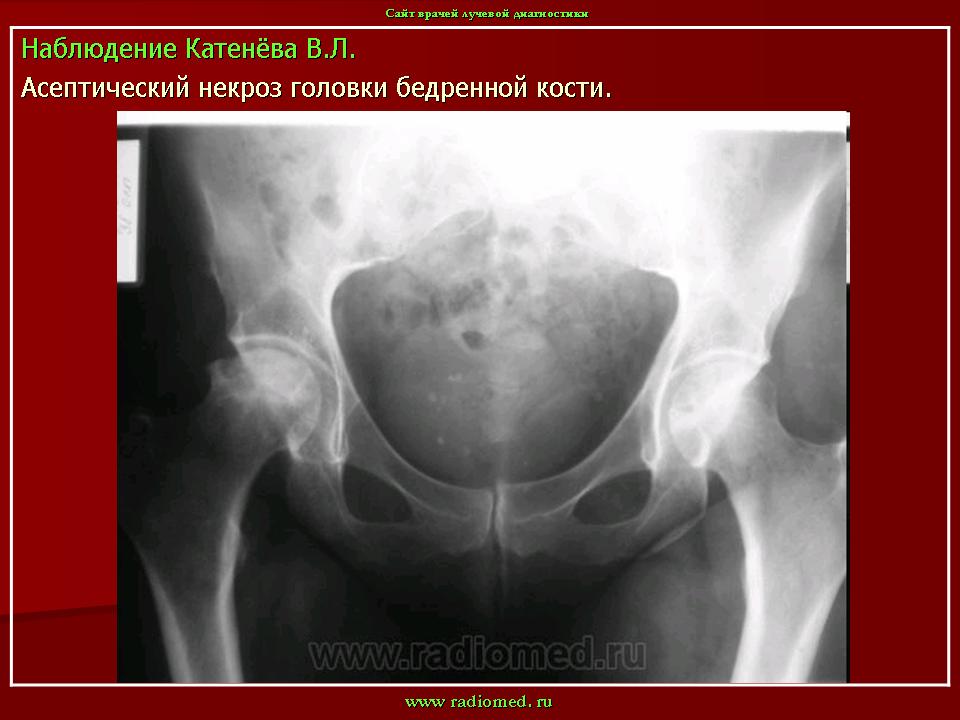

Остеохондропатия головки бедренной кости

(болезнь Легга-Кальве-Пертеса)

Заболевание протекает по типу первичного асептического некроза и возникает вследствие сосудистых расстройств в субхондрально расположенном губчатом веществе головки бедренной кости. В качестве этиологических факторов рассматриваются микротравма, перегрузка на фоне конституциональной предрасположенности, нарушение нормального процесса окостенения эпифиза головки бедренной кости в возрасте 3-8 лет (Пертес-возраст), связанное с субкритическим его кровоснабжением вследствие врожденного недоразвития локальной сосудистой сети. Не исключается наследственный фактор в развитии заболевания, а также влияние очагов хронической инфекции. В последние десятилетия высказывается мнение о диспластической природе патологии, согласно которому причиной сосудистых нарушений и некроза головки является патологическая ориентация компонентов тазобедренного сустава.

Изменения на рентгенограммах зависят от стадии процесса.

В I стадии (асептиче­ского некроза губчатой кости эпифиза и костного мозга) изменения отсутствуют либо незначительные: в виде остеопороза костей, образующих тазобедренный сустав, извилистости и неравномерности хрящевой эпифизарной пластинки, неоднородности и пятнистости шейки бедра, некоторого расширения щели сустава.

Во II стадии (импрессионного перелома) головка бедренной кости утрачивает характерную трабекулярную структуру, шейка бедра становится более остеопоротичной. Суставная щель отчетливо расширяется по сравнению со здоровым тазобедренным суставом. Эпифиз головки уплотняется, склерозируется и деформируется (вследствие сохраняющейся нагрузки).

В III стадии (фрагментации эпифиза) суставная щель по-прежнему расширена, головка сплющена и как бы разделена на отдельные глыбки или неправильной формы мелкоочаговые фрагменты. Обычно определяется от 2 до 5 таких фрагментов, а иногда и больше. Вертлужная впадина уплощается.

В IV стадии (репарации) определяется формирование новых костных балочек, эпифиз полностью замещается новообразованной костью с участками просветления в центре.

В V стадии (конечной) завершается структурная перестройка и восстановление формы головки и шейки бедра. Суставная щель суживается и приближается по своей величине к нормальной. Если лечение было правильным, форма восстановленной головки незначительно отличается от сферической; в противном случае формируется грибовидная головка с укороченной расширенной шейкой. При этом вертлужная впадина не полностью покрывает увеличенную деформированную головку, что впоследствии приводит к развитию вторичного коксартроза.